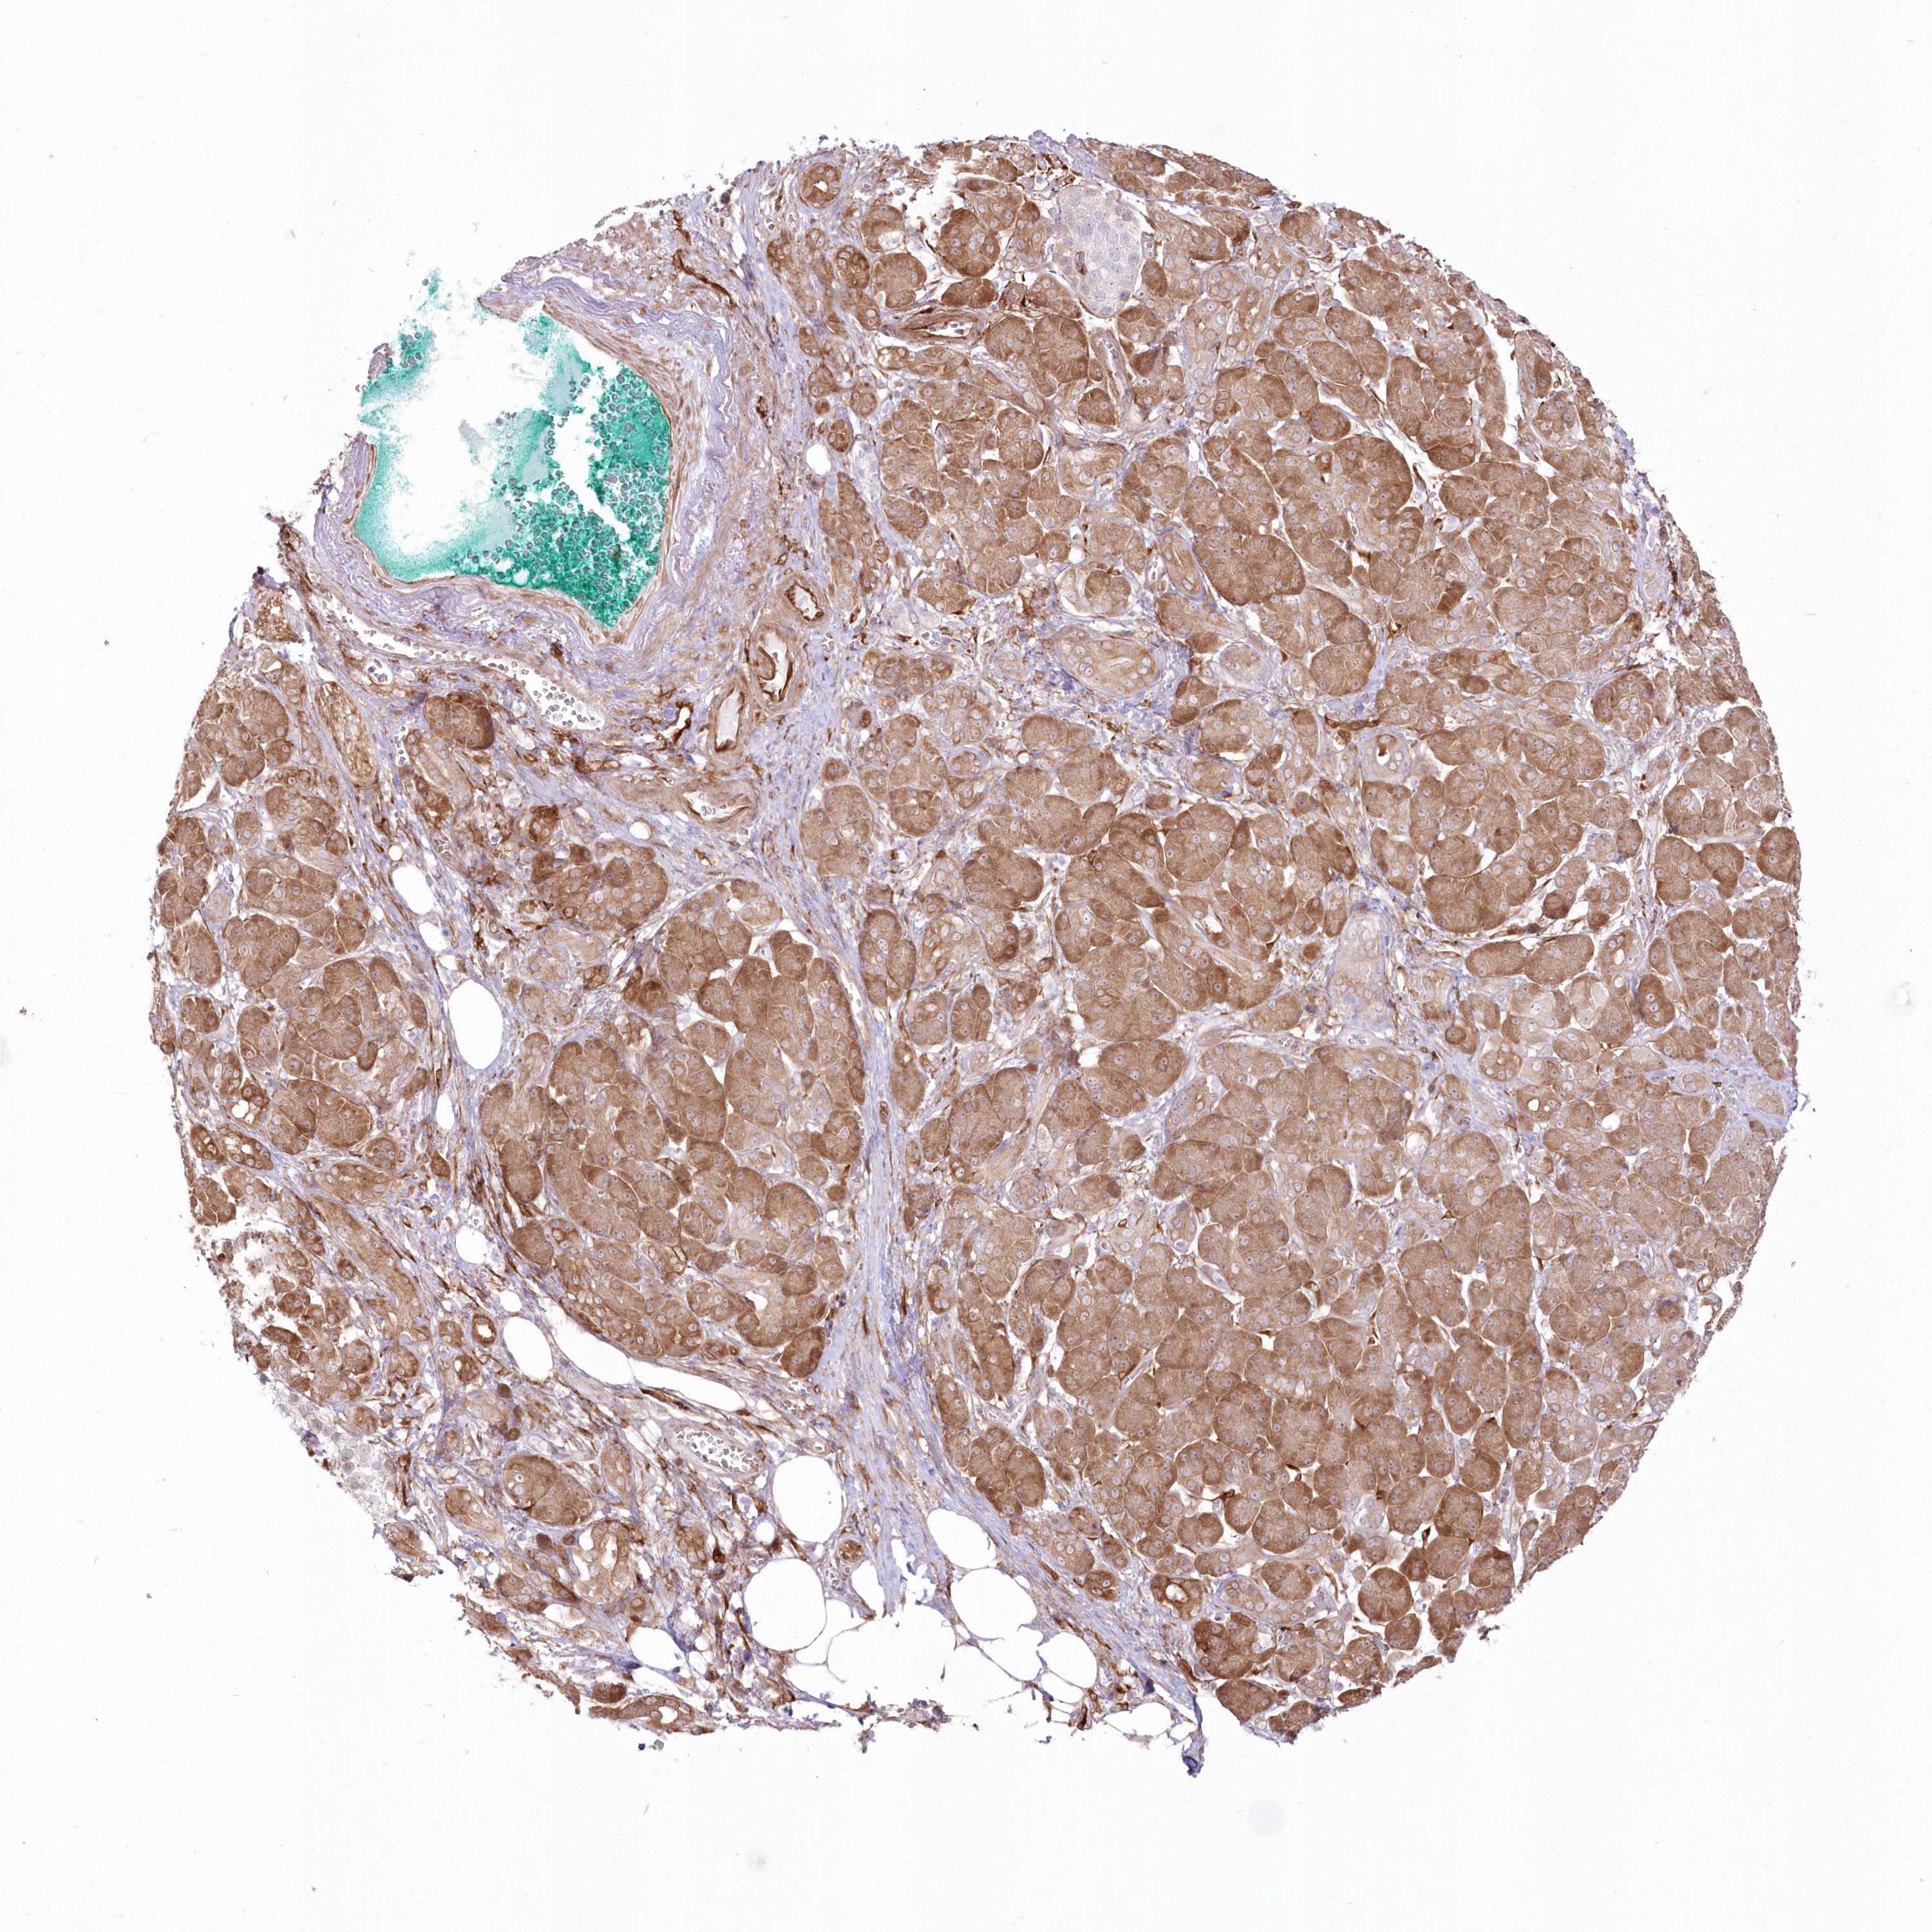

PANCREATIC CANCER - Protein expressioni

A mouse-over function shows sample information and annotation data. Click on an image to view it in a full screen mode. Samples can be filtered based on level of antibody staining by selecting one or several of the following categories: high, medium, low and not detected. The assay and annotation is described here.

Note that samples used for immunohistochemistry by the Human Protein Atlas do not correspond to samples in the TCGA dataset.

Antibody stainingi

Antibody staining in the annotated cell types in the current human tissue is reported as not detected, low, medium, or high, based on conventional immunohistochemistry profiling in selected tissues. This score is based on the combination of the staining intensity and fraction of stained cells.

Each image is clickable and will lead to virtual microscopy that enables deeper exploration of all samples and also displays staining intensity scores, fraction scores and subcellular localization as well as patient and tissue information for each sample.

Antibody HPA036471

Staining

High

Medium

Low

Not detected

Intensity

Strong

Moderate

Weak

Negative

Quantity

>75%

75%-25%

<25%

None

Location

Nuclear

Cytoplasmic/membranous

Cytoplasmic/membranous,nuclear

Adenocarcinoma, NOS